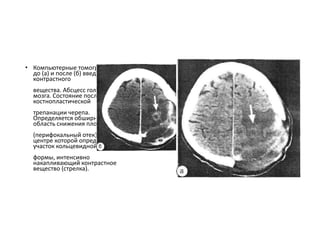

• Компьютерные томограммы до(а) и после (б) введения контрастного вещества. Абсцесс головного мозга. Состояние после костнопластической трепанации черепа. Определяется обширная область снижения плотности (перифокальный отек), в центре которой определяется участок кольцевидной формы, интенсивно накапливающий контрастное вещество (стрелка).